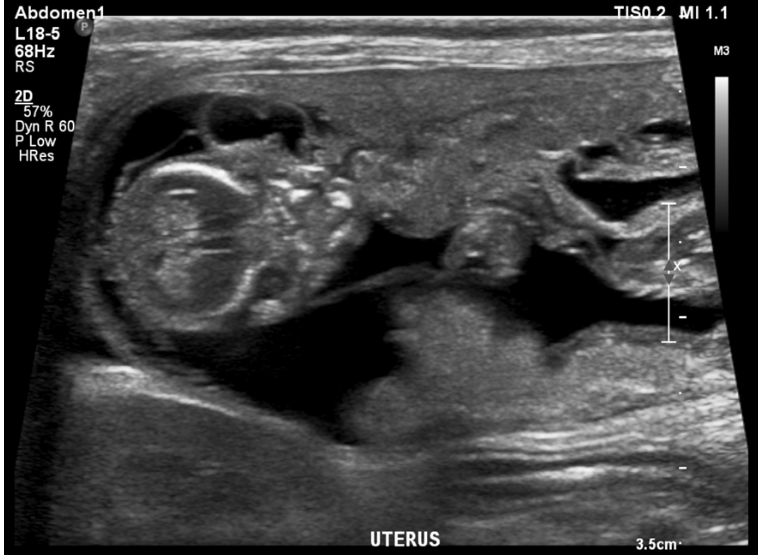

What is shown in this image?

A

pyometra